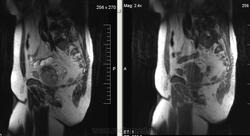

Метастазы рака простаты, кроме измений в позвонках видна сама первичная опухоль и лимфатические узлы (общий и наружный подвздошные слева, ещё один в левой подвздошной ямке).

После добавления томограмм исследования органов малого таза картина стала ещё печальнее...

Да, запустил пациент. До этого были проблемы с мочеиспусканием, рези, болезненность. Лечился самостоятельно от простатита, отмечал временное улучшение.